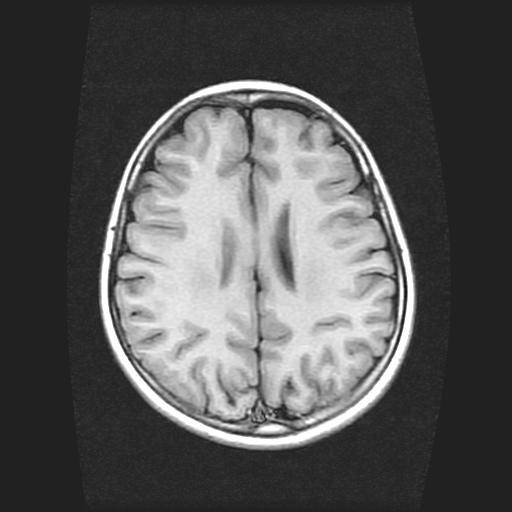

标题: PED0378:女孩9岁,癫痫,看能否停药 [打印本页]

标题: PED0378:女孩9岁,癫痫,看能否停药

9岁女孩,三岁时诊断为癫痫,一直服丙戊酸钠,现患者一般情况良好,家长复查核磁片,看能否停药..

未见异常信号灶.

未发现异常信号。

停药要结合临床,如无发作可以停。